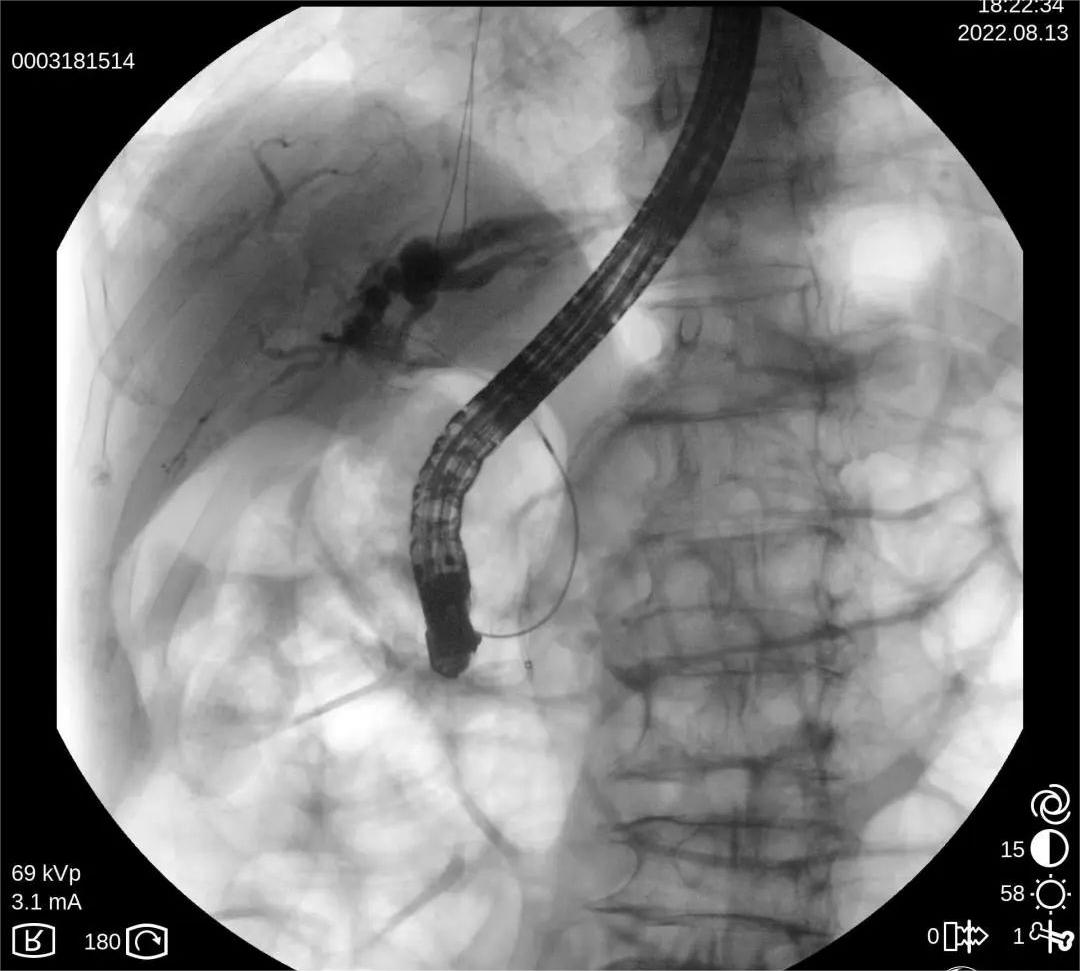

C型臂X光机该设备具有C型的机架,由产生X射线球管、采集图像的影像增强器、CCD摄像机和图像处理工作站组成。通常情况下科室又把小C叫做C臂X光机、C臂机、C型臂、小C臂、移动式C型臂等,其主要用于骨科手术打钉、整骨、复位;外科植入起搏器、取体内的异物、部分造影术、部分介入手术;以及配合臭氧机治疗疼痛、小针刀治疗、妇科输卵管导引手术等。

操作便捷:移动式C型臂X光机使手术中的使用变得更加及时便捷,为手术提供透视服务。

C型臂发出的射线进入病人身体后,只有 1%左右的射线穿过病人到达增强器表面,如下图

当射线进入人体后,1%穿过人体进入增强器,其余 80%-90%的射线被病人吸收,10%-20%的射线被人体散射。如下图